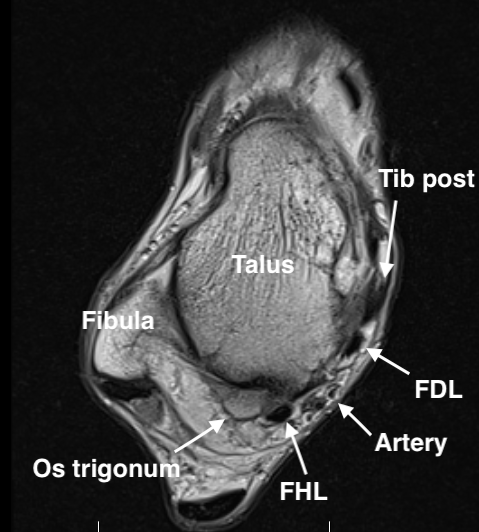

MRI

Findings

- synovitis over posterolateral process talus

- fluid in sheath about FHL

- edema around os trigonum

- edema posterior tibia bone

- thickened posterior capsule

Os trigonum FHL tenosynovitis with posterior ankle joint soft tissue

Stieda's process with ankle joint effusion